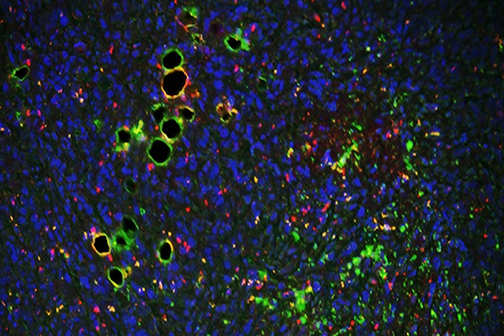

Scientists at LSU Health New Orleans’ Neuroscience Center of Excellence, led by Nicolas Bazan, MD, PhD, Boyd Professor and Director, have identified a new mechanism that regulates a protein key for cell survival. It appears to protect against the excessive oxidative stress that precedes the development of neurodegenerative diseases of the brain and eye. More

A study led by Nicolas Bazan, MD, PhD, Director of the LSU Health New Orleans Neuroscience Center, pinpointed which cells within specific areas of the brain are involved in post-stroke response and found that the delivery of precursors of Elovanoids, a class of molecules that synchronize cell-to-cell communication and neuroinflammation/immune activity in response to injury, improved neurological deficit in an experimental model of ischemic stroke. More

LSU Health New Orleans Study Identifies a Potential New Approach to PTSD Treatment

LSU Health New Orleans Researchers Discover Potential New Rx Strategy for Ischemic Stroke